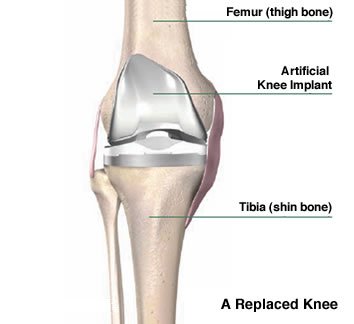

Best Knee Replacement Surgeon in Jabalpur is Dr. Abhinav Kesarkar If you are suffering from chronic knee pain, arthritis, or joint stiffness that limits your daily activities, it’s time to consult the best knee replacement surgeon in Jabalpur. Moreover, with advanced surgical techniques, modern implants, and personalized post-operative care, you can quickly regain mobility and live pain-free again.

The latest knee implant technology